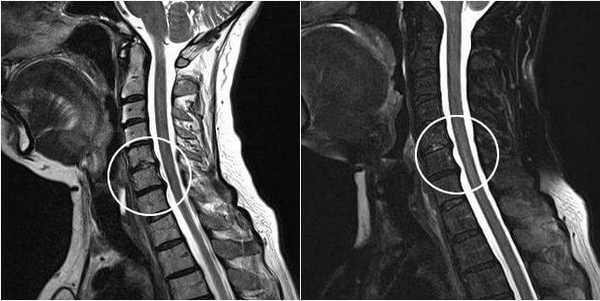

Диагностику остеохондроза позвоночника проводит невролог или вертебролог. На начальном этапе производят рентгенографию позвоночника в 2-х проекциях. При необходимости могут сделать съемку отдельного позвоночного сегмента и съемку в дополнительных проекциях. Для диагностики межпозвонковой грыжи, оценки состояния спинного мозга и выявления осложнений остеохондроза применяют магнитно - резонансную томографию (МРТ позвоночника). Большую роль играет МРТ в дифференциальной диагностике остеохондроза и других заболеваний позвоночника: туберкулезный спондилит, остеомиелит, опухоли, болезнь Бехтерева, ревматизм, инфекционные поражения. Иногда в случаях осложненного остеохондроза шейного отдела позвоночника необходимо исключение сирингомиелии. В некоторых случаях при невозможности проведения МРТ показана миелография.

МРТ поясничного отдела позвоночника. 1- выраженная дегидратация межпозвонковых дисков во всех сегментах. 2- дегидратация в сегментах L3-L4, L4-L5 справа (разные пациенты)

Прицельное исследование пораженного межпозвонкового диска возможно при помощи дискографии. Электрофизиологические исследования (вызванные потенциалы, электронейрография, электромиография) применяют для определения степени и локализации поражения нервных путей, наблюдения за процессом их восстановления в ходе терапии.